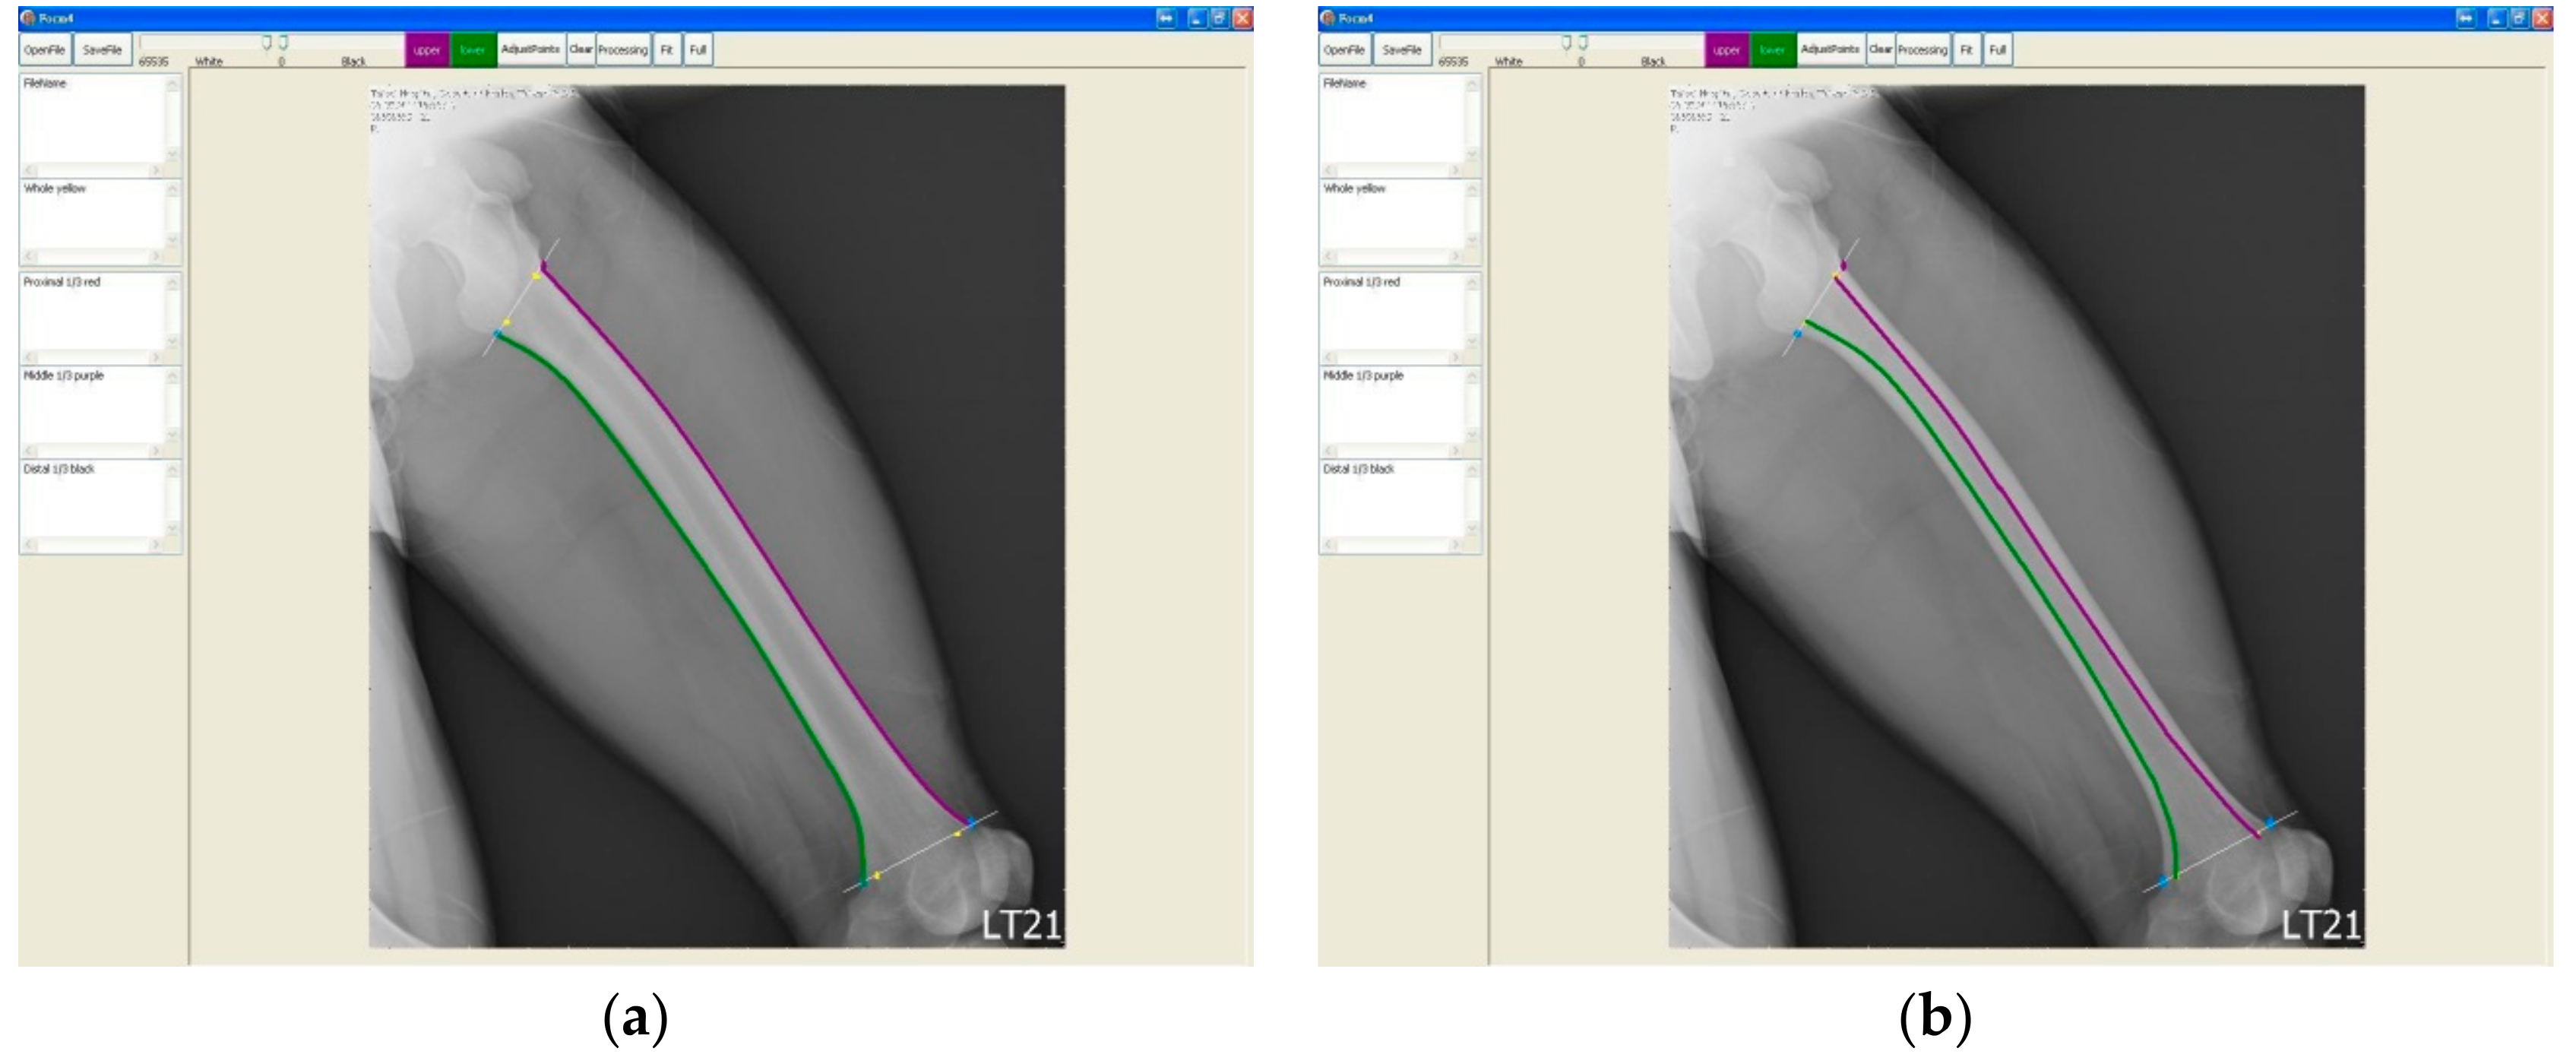

Once we had determined the proximal and distal ends, we started to draw the upper and lower borders on the image from the proximal end to the distal end, respectively. For each image, we drew the outlines of the femur and the borders of the medullary canal to calculate the curvature of the femur (cortical bow) (Figure 4a) and that of the interior medullary canal (medullary bow) (Figure 4b).

Figure 4. The marked (drawn) outline of cortical border (a) and the marked (drawn) outline of medullary canal (b).